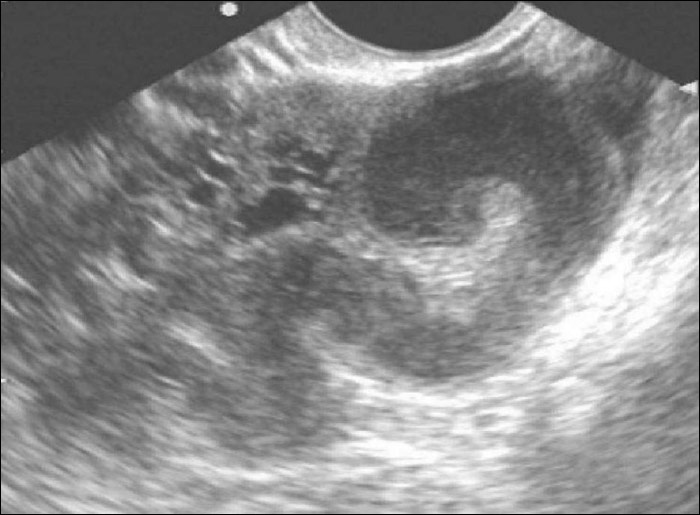

По данным трансвагинального УЗИ или трансабдоминального УЗИ малого таза позади матки определяется расширенная фаллопиева труба неоднородной эхогенности с мелкодисперсной взвесью. Исследование периферической крови отражает картину воспаления: лейкоцитоз, сдвиг в лейкоформуле влево, нарастание СОЭ, положительный тест на СРБ. Для определения инфекционных возбудителей производится бактериологический посев мазка на микрофлору.